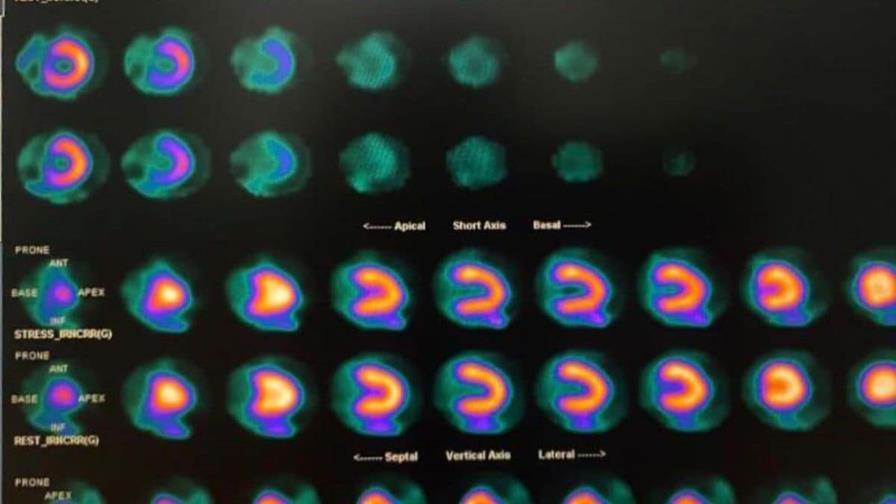

Los Centros de Diagnóstico y Medicina Avanzada y de Conferencias Médicas y Telemedicina (Cedimat) marcaron un nuevo hito en la medicina dominicana al realizar con éxito la primera gammagrafía cardíaca utilizando el vasodilatador Regadenoson, un fármaco de última generación que mejora significativamente la precisión y seguridad de los estudios de perfusión miocárdica.

La gammagrafía cardíaca, también conocida como estudio de perfusión miocárdica, evalúa el flujo sanguíneo al corazón durante el reposo y el estrés. El Regadenoson es un vasodilatador selectivo aprobado por la Administración de Alimentos y Medicamentos, en sus siglas en inglés (FDA), ampliamente utilizado en los centros cardiovasculares más prestigiosos del mundo. A diferencia de otros agentes farmacológicos, su uso permite una mayor tolerancia por parte del paciente, menos efectos secundarios y una mayor exactitud diagnóstica en la evaluación de la perfusión del músculo cardíaco.

Este medicamento se utiliza en pacientes que no pueden realizar ejercicio físico, para simular el esfuerzo cardíaco y detectar obstrucciones o áreas con irrigación reducida. El Regadenoson provee mayor seguridad y tolerancia, reduciendo significativamente los efectos secundarios como el dolor de cabeza, hipotensión o broncoespasmo, o las arritmias inducidas por la Dobutamina. Este nuevo fármaco es de administración más simple, lo que acorta el tiempo total del estudio y se puede utilizar en pacientes con asma o enfermedad pulmonar crónica leve, que antes no eran candidatos por riesgo de complicaciones.